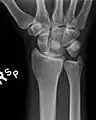

Півмісяцева кістка при вивиху